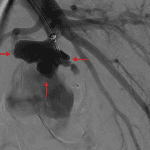

Sample ReportFindings concerning for necrotizing pneumonia in the left lower lobe with a large associated pulmonary arterial pseudoaneurysm. Recommend conventional pulmonary arteriogram and possible endovascular coiling.